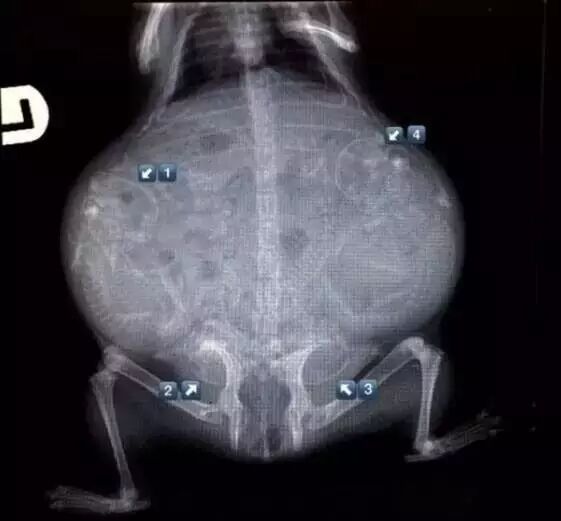

怀孕的乌龟

奇趣百科 涨姿势 · 17种怀孕动物X光照片,大开眼界!-怀孕期